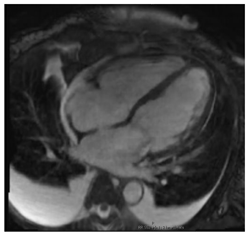

6.4. CMR Findings

CMR is a sensitive diagnostic tool for CS, with studies yielding sensitivities between 75 and 100% []. SSFP cine imaging is used to assess for regional wall thinning or thickening, aneurysmal or dyskinetic segments, and biventricular systolic function []. In CS, native T1 mapping may be focally increased in regions of fibrosis or edema []. Native T2 mapping may also be focally increased in regions of edema if there is active inflammation []. Black-blood T2 weighted imaging can improve the detection of myocardial edema and was found to have comparable diagnostic performance to FDG-PET in a retrospective study [].

The hallmark of CMR in CS is the evaluation of LGE. LGE can reflect edema in the acute inflammatory phase and replacement fibrosis in the chronic stage of CS. LGE is often patchy, mid-myocardial and/or subepicardial, and involves the basal LV segments and RV portion of the septum [,]. Sometimes, the LGE may be transmural or subendocardial, mimicking an ischemic pattern []. FDG-PET imaging complements CMR, and combining both modalities has been shown to enhance the certainty of CS diagnosis []. In a meta-analysis of histologically proven cardiac sarcoidosis, Okasha et al. found that the lack of any myocardial LGE or the presence of isolated midmyocardial, subendocardial, or transmural LGE were rarely to never present []. This highlights the potential role of certain LGE patterns on CMR in excluding cardiac involvement in sarcoidosis. Key CMR findings in CS are summarized in Table 4.